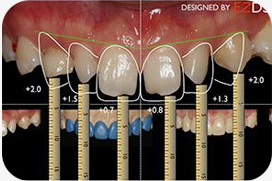

1数字化微笑分析

确定前牙牙龈缘高度、长宽比例、大小比例,绘制牙齿形态,完成DSD设计